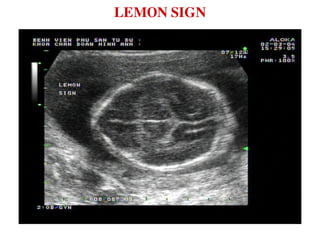

LEMON SIGN